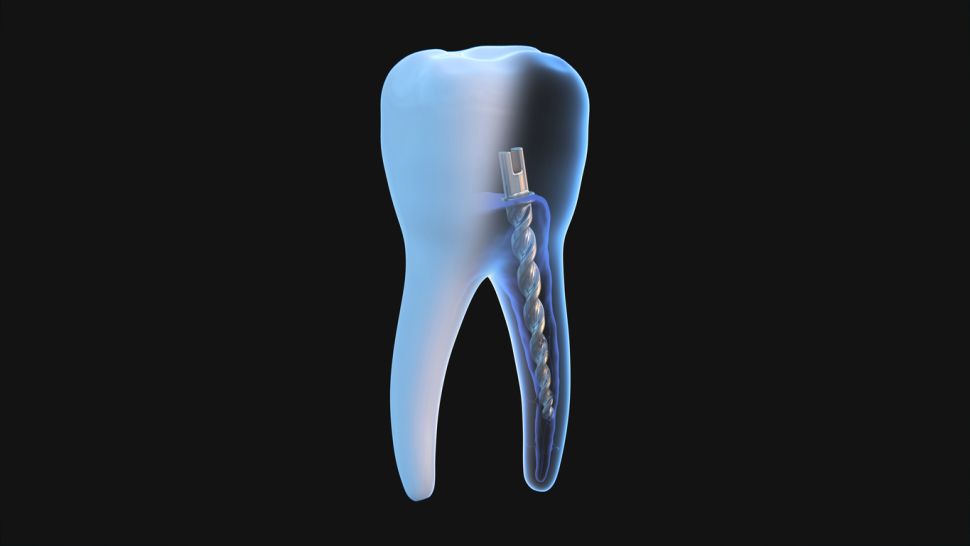

Щифтовото изграждане включва използването на щифт (пост) и композитен или друг материал за възстановяване на загубената зъбна структура. Той се поставя в кореновия канал на зъба, който предварително е бил обработен и пломбиран след кореново лечение. След това около него се изгражда новата структура на зъба.

- Метални щифтове: Традиционно използвани поради своята здравина и устойчивост. Те могат да бъдат направени от различни метали като титан или злато.

- Фиброоптични щифтове: Изработени от материали като фибростъкло или въглеродни влакна, които са по-еластични и биосъвместими. Те имат по-добра естетика и са предпочитани за предни зъби.

- Керамични щифтове: Осигуряват отлична естетика и са устойчиви на корозия. Те обаче са по-крехки в сравнение с металните.